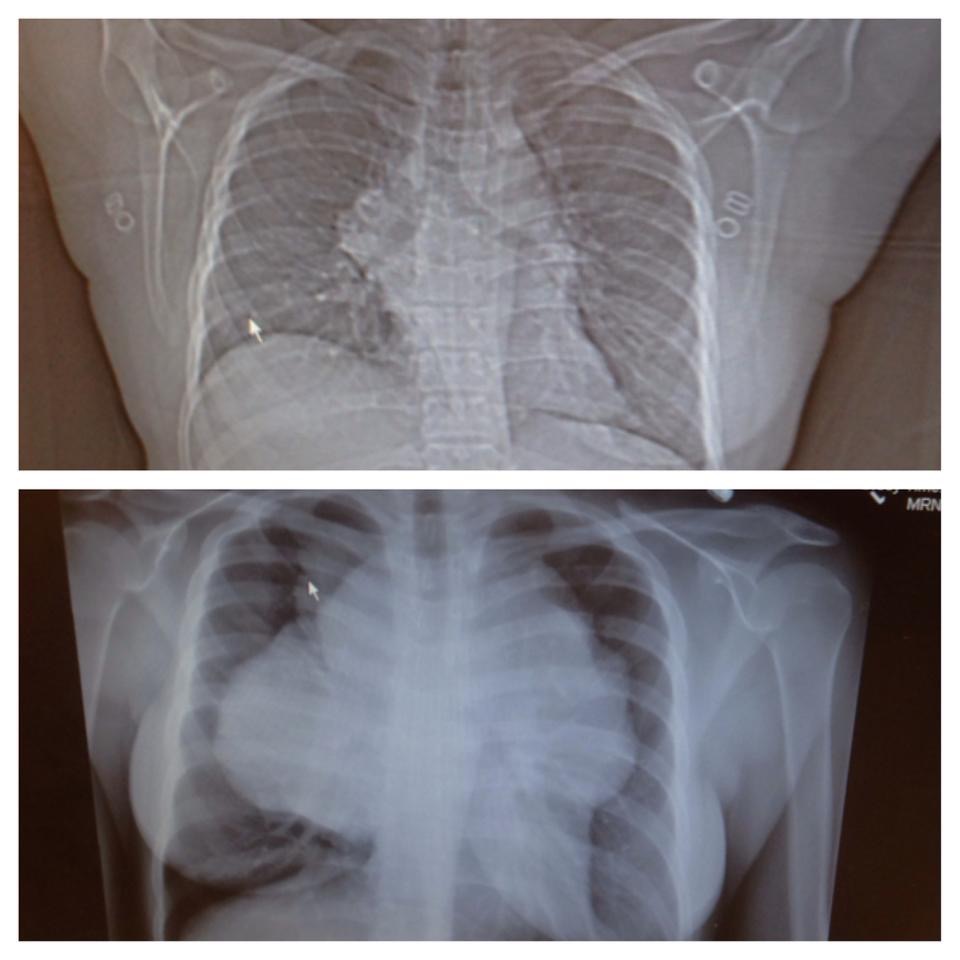

Me and my mom went to just get examined and get the hell out of there, but obviously that wasn’t the case. The X-ray revealed a mass that spread approximately 18-20 cm across my entire chest and into my shoulders. One doctor stated, “I’ve never seen anything this massive before.” My family’s world completely stopped as we all struggled to grasp the news.

I was completely frozen from that point on. I remember them talking, my mom crying with black mascara down her face, the doctors asking if I’d like to see what the x-ray looked like and me responding with ‘no’ because I was so scared to face reality.